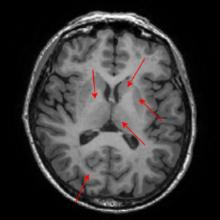

Non-human primates (NHPs) serve as critical models for understanding human brain function and neurological disorders due to their close evolutionary relationship with humans. Accurate brain tissue segmentation in NHPs is critical for understanding neurological disorders, but challenging due to the scarcity of annotated NHP brain MRI datasets, the small size of the NHP brain, the limited resolution of available imaging data and the anatomical differences between human and NHP brains. To address these challenges, we propose a novel approach utilizing STU-Net with transfer learning to leverage knowledge transferred from human brain MRI data to enhance segmentation accuracy in the NHP brain MRI, particularly when training data is limited. The combination of STU-Net and transfer learning effectively delineates complex tissue boundaries and captures fine anatomical details specific to NHP brains. Notably, our method demonstrated improvement in segmenting small subcortical structures such as putamen and thalamus that are challenging to resolve with limited spatial resolution and tissue contrast, and achieved DSC of over 0.88, IoU over 0.8 and HD95 under 7. This study introduces a robust method for multi-class brain tissue segmentation in NHPs, potentially accelerating research in evolutionary neuroscience and preclinical studies of neurological disorders relevant to human health.